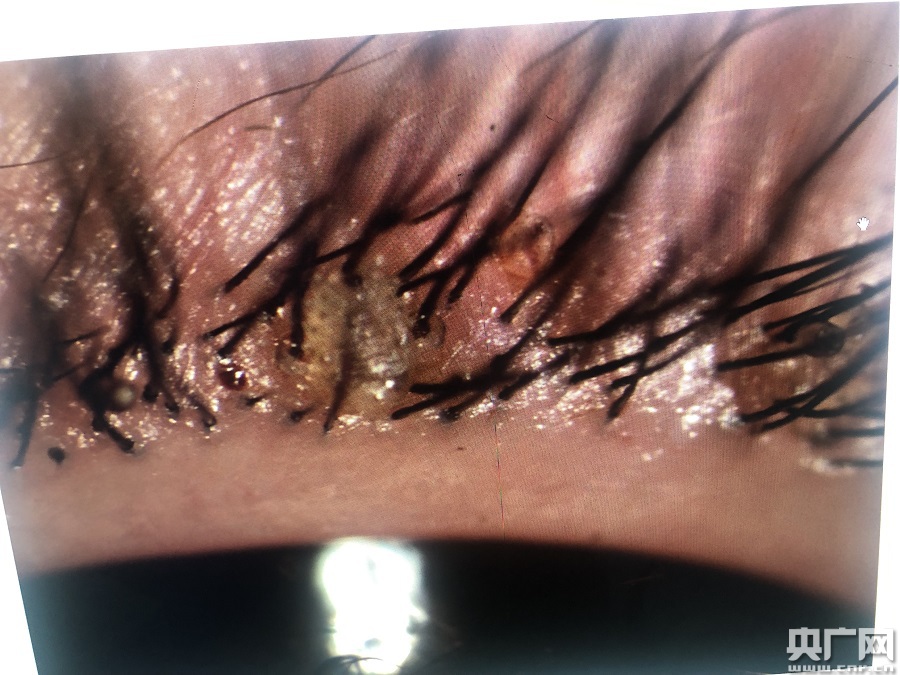

小女孩眼睫毛上長(zhǎng)滿(mǎn)陰虱(央廣網(wǎng)發(fā) 通訊員供圖)

該院眼表及角膜病專(zhuān)科副主任醫(yī)師商旭敏接診后,在裂隙燈下仔細(xì)查看,發(fā)現(xiàn)甜甜的雙眼局部紅腫明顯,睫毛根部竟然掛著幾十粒黑色未孵化的蟲(chóng)卵及白色孵化后的卵殼。仔細(xì)觀察之下,還有白色的蟲(chóng)子在蠕動(dòng)。

該院門(mén)診副護(hù)士長(zhǎng)王亞靈先在裂隙燈下夾起吸附在瞼緣上的陰虱、蟲(chóng)卵,剪去睫毛,反復(fù)確認(rèn)陰虱和蟲(chóng)卵全部除盡后,再進(jìn)行局部清洗、上藥。“經(jīng)查實(shí),這些小蟲(chóng)子是陰虱,有20多只。取出的睫毛、成蟲(chóng)還有蟲(chóng)卵都進(jìn)行統(tǒng)一焚燒。我從醫(yī)幾十年,有見(jiàn)過(guò)眼內(nèi)長(zhǎng)陰虱的,不過(guò)長(zhǎng)20多只,這還是第一次碰到!蓖鮼嗢`說(shuō)。